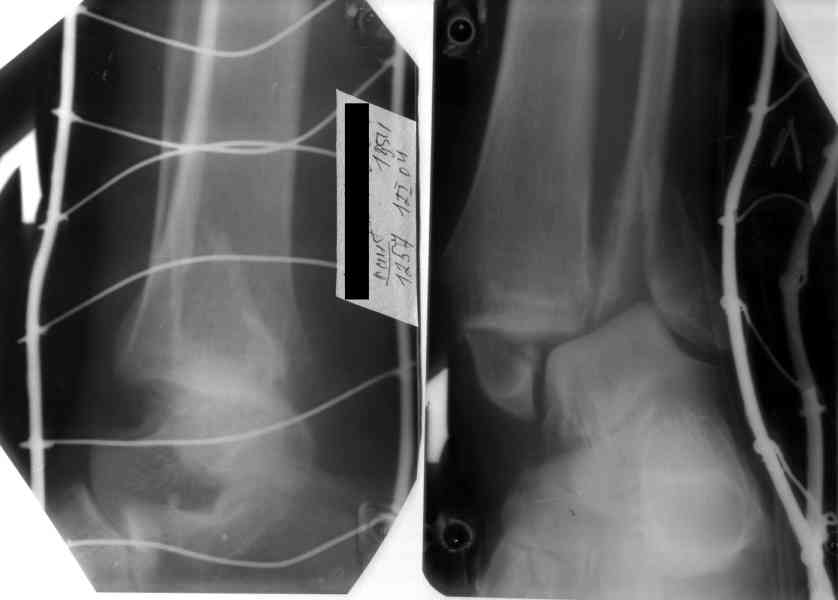

В течение длительного времени у нас принят этот способ фиксации, по показаниям конечно. Тактика такая: После репозиции и ТАФ стопы, гипсовая шина обязательно. Ч/з 7 дней Рентгенконтроль. Спицы удаляем через 1,5 мес, и затем продлеваем гипсовую иммобилизацию до 2-2,5 мес. Результатами я честно говоря доволен. Если спицы убрать раньше или вести совсем без них, то очень вероятно вторичное смещение. Удачи!

На 4-й неделе убрал спицы, с 7-й недели начал ЛФК, дозированную нагрузку, физиопроцедуры, массаж. Назначил хондропротекторы. Получилось вот что.

Rg-05.JPG

Удалены спицы, а гипса не было? 3-х лодыжечный перелом фиксировать 4 недели недостаточно. Что и подтверждается на последнем снимке - есть тенденция к подвывиху кнаружи, кзади... Что будет дальше, когда пациент начнет давать полную нагрузку?

СМ> На 4-й неделе убрал спицы, с 7-й недели начал ЛФК, дозированную

СМ> нагрузку, физиопроцедуры, массаж. Назначил хондропротекторы.

СМ> Получилось вот что.

Малоберцовая выглядит коротковатой. Профиль как-то мутный. Вообще, неплохо было бы сделать снимки в сравнении со здоровой.